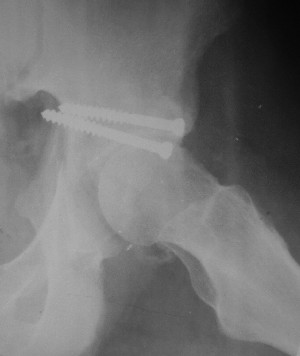

19/05/03

Больной 18 мая 2003 года в автоаварии получил перелом левой вертлужной впадины, вывих бедра. Госпитализирован в один из стационаров области.Вывих вправлен. В последствии бедро вывихивалось еще дважды. На консультацию был представлен снимок от 19.05.03г., больной переведен к нам 3.06.03г. Снимок при поступлении - перелом впадины, задне-верхний вывих бедра. 05.06.2003 г. выполнено открытое вправление вывиха левого бедра и остеосинтез стенки вертлужной впадины двумя винтами. Послеоперационный период без осложнений. Объем движений в левом тазобедренном суставе восстановился полностью. Выписан на амбулаторное лечение в удовлетворительном состоянии с рекомендациями 3 месяца ходить на костылях без нагрузки на оперированную конечность. На контрольных рентгенограммах левого тазобедренного сустава 13.10.2003 г. - признаки консолидации перелома; плотность, форма головки и состояние суставных поверхностей удовлетворительные. Разрешена дозированная осевая нагрузка, на конечность с использованием дополнительной опоры. 19.12.2003 г. больной обратился с жалобами на боли в левом тазобедренном суставе. На рентгенограммах левого тазобедренного сустава 19.12.2003 г., 20.02.04г. - асептичекий некроз головки бедра. 5.04.04г. - эндопротез. Сейчас ходит без трости, не хромает. Особенность эндопротезирования - при удалении винтов прослежена линия перелома заднего края впадины и предложено установить чашку несколько меньшего диаметра, чтобы она была покрыта несломанной частью.